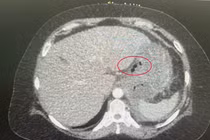

Tại Trung tâm Phẫu thuật Gan mật - Tiêu hoá căn cứ trên các kết quả xét nghiệm, siêu âm, chụp cắt lớp và theo dõi lâm sàng, anh L được chẩn đoán thủng ruột non do dị vật và được chỉ định phẫu thuật cấp cứu ngay trong đêm.

Trong khi mổ, ê kíp phẫu thuật phát hiện ổ bụng của bệnh nhân có dịch đục và bị nhiễm trùng nặng. Vùng tiểu khung, ruột thừa vị trí hố chậu phải viêm xung huyết. Một ổ áp xe tại đoạn ruột non vị trí cách góc hồi manh tràng khoảng 1 mét, nguyên nhân là mảnh xương cá dài 4 cm đâm thủng ruột non. Cách đó 10 cm, có một túi thừa Meckel lớn.